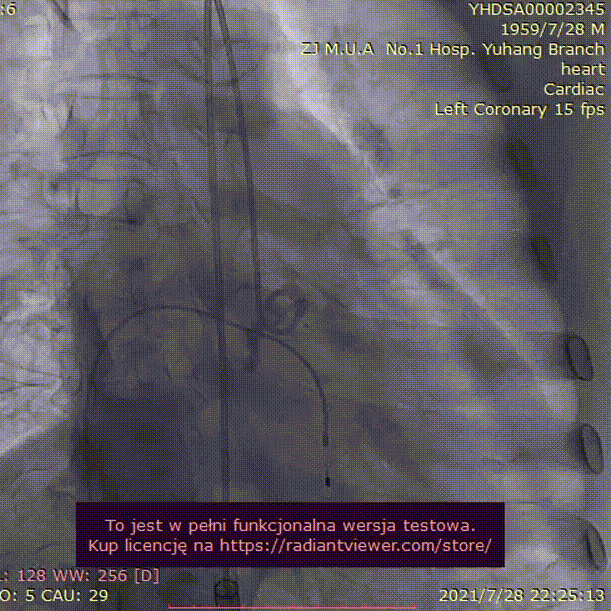

病例3 - 3D打印评估冠脉高风险功能型二叶瓣

男性,62岁,因“反复胸闷胸痛半年,再发1月”入院。

手术难点及策略:

手术过程:

20mm球囊预扩

(无腰征,少量瓣周漏)

TAV24 瓣膜释放前定位

释放过程

植入后造影

术后压差1mmHg

术后结果:测左室-主动脉平均跨瓣压差3mmHg。

术中经食道心超评估: